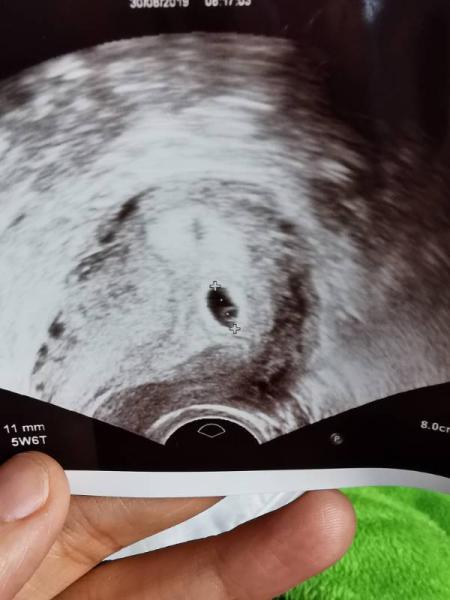

Hallo ihr lieben. Ich war heute bei 5+6 beim Arzt, man hat eine Fruchthöhle gesehen und einen Dottersack darin. Sie konnte ein Baby erahnen. Nächste Woche Freitag muss ich wieder hin. Aber kann mir jemand sagen was der Fleck daneben ist? Wird das noch eine Fruchthöhle? Oder einfach nur ein Schatten oder sowas. Eine Freundin hat mir den Floh ins Ohr gesetzt es könnten ja 2 sein. Hätte ja gefragt aber ich hab mir das Bild danach erst angeschaut. Sah es bei jemandem vielleicht auch so aus? :)

Bild zu 2 Fruchthöhlen? - Forum für April - Mamis